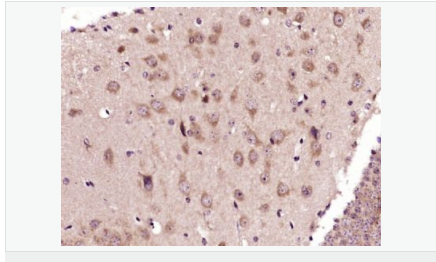

| 产品应用 | WB=1:500-2000 IHC-P=1:100-500 IHC-F=1:100-500 Flow-Cyt=3ug/test ICC=1:100-500 IF=1:100-500 (石蜡切片需做抗原修复) not yet tested in other applications. optimal dilutions/concentrations should be determined by the end user. |